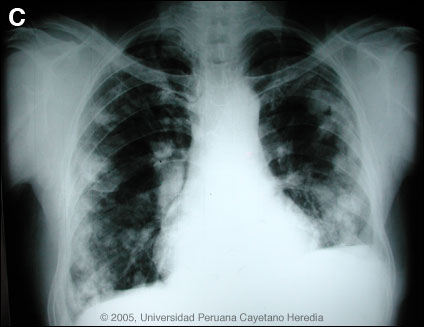

Epidemiology: Born in an agricultural community in Huaraz high in the Andes but has lived in Lima for 30 years. No contacts or history of TB. No ill relatives. Non-smoker. Physical Examination: Afebrile. HEENT normal. No lymphadenopathy or hepatosplenomegaly. Stool heme negative. Bilateral thoracotomy scars. Laboratory Examination: Hct 42%. WBC 14,200 with 80 segs, 2 bands, 14 lymphs, 1 eosinophil. LFTs normal. Sputum for AFB and culture negative. CXR and chest CT scan are shown in Images A and B. CT scan of the abdomen was normal.

![]() Discussion: ELISA and Western Blot were strongly positive for E. granulosus. Records subsequently obtained indicated that 12 years earlier he had had a spontaneous rupture of a large solitary left-sided pulmonary hydatid cyst. The expectoration of large amounts of clear salty fluid is highly characteristic of this catastrophic event. No medical therapy had been given peri- or post-operatively. Human hydatid disease secondary to Echinococcus granulosus is caused by the larval form of this dog tapeworm. Humans ingest the tapeworm eggs in environments contaminated by canine feces and become accidental intermediate hosts. Sheep are the normal intermediate hosts. Larval cysts expand slowly over years or decades becoming symptomatic as they impinge on other structures by virtue of their size. Spontaneous cyst rupture as occurred here happens in the minority of cases but is not rare. The cysts contain hundreds of viable scoleces capable of becoming adult tapeworms upon ingestion by a definitive host such as the dog. The germinal membrane lining the cyst produces new scoleces on an ongoing basis. Each scolex is capable of becoming a new daughter cyst either within the original cyst or elsewhere should the original cyst rupture or be ruptured. Hydatid disease is common in sheep-raising areas worldwide. Most primary infections involve a single cyst. 65% of solitary cysts are found in liver, 25% in lung and the rest in a wide variety of other organs including kidney, spleen, heart, bone and brain. In patients with a pulmonary cyst, approximately 15% will also have a hepatic cyst. Serology is usually positive with hepatic cysts but sensitivity drops below 50% with solitary pulmonary cysts even when the cyst is large. With the large burden of disease in this patient?s lung a positive serology would be expected. The 2 subsequent chest surgeries in our patient were to resect further cystic hydatid lesions that had developed secondary to seeding of the thoracic cavity during the initial catastrophic event. 7 years prior to presentation to us, the patient received a 1-year course of intermittent albendazole and then 5 years earlier began to receive 6 separate 2-month courses over the following 2 years. At the end of this therapy only a few small residual cysts apparently remained. Praziquantel is the most potent scolicidal drug and is the drug of choice for adult tapeworms. However, praziquantel cannot penetrate the hydatid cyst wall so is only useful as an acute therapy when a cyst ruptures (spontaneously or due to surgical mishap) and scoleces are lying free before encysting again. Albendazole is the therapy of choice for intact cysts that are not operable, such as when there are multiple or diseminated cysts. A trial of Albendazole may also be considered for solitary cysts that are less than about 10 cm. Response is generally slow and only complete in a minority of cases. Surgical resection is the therapy of choice for large solitary cysts. Our patient was begun on continuous albendazole therapy and a follow-up CXR obtained after 7 months is shown in Image C. The plan is to continue therapy for a minimum of 1 year and perhaps as long as 2 years. Liver function tests remain normal in this patient.